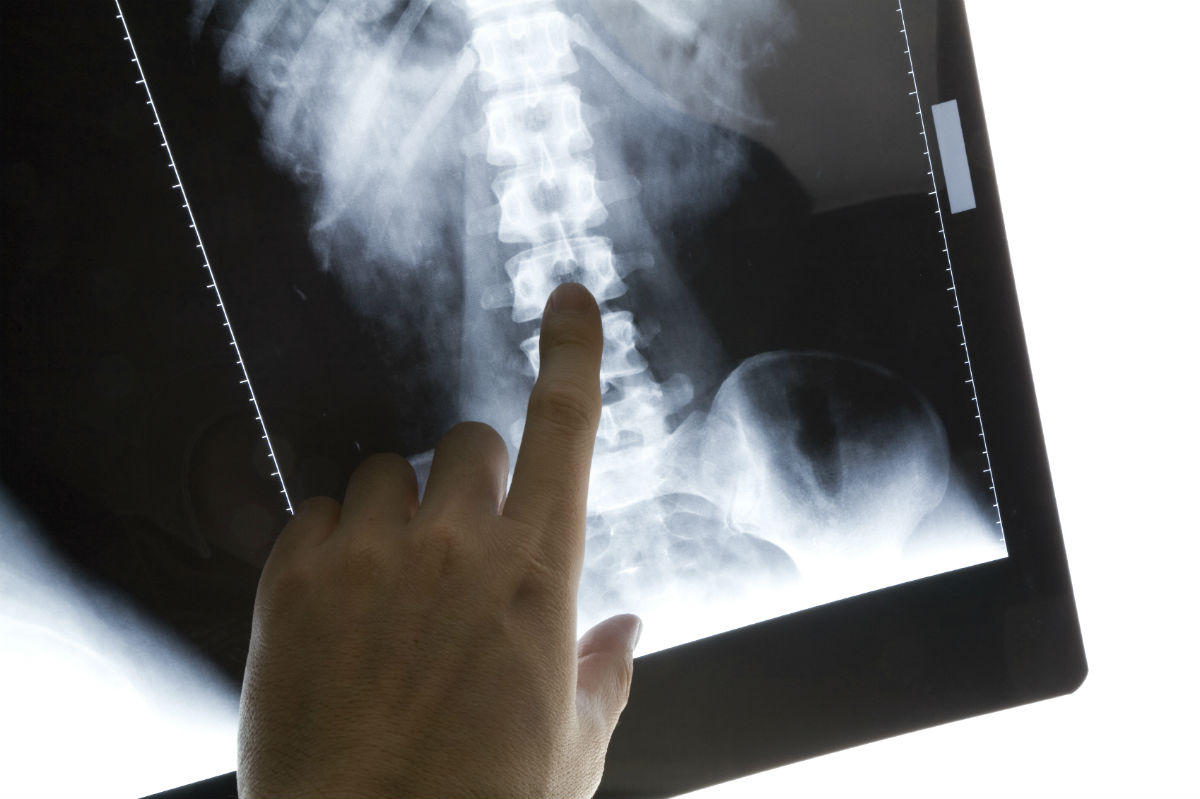

Motorcycle Accidents and Spinal Injuries

One of the most devastating and live changing injuries resulting from a motorcycle accident is a spinal injury. The spinal cord controls communication of the brain with the rest of the body, and any injury to the spine can cause permanent damage, leading to paralysis. Types of Spinal Injuries Spinal injuries can be classified into complete …